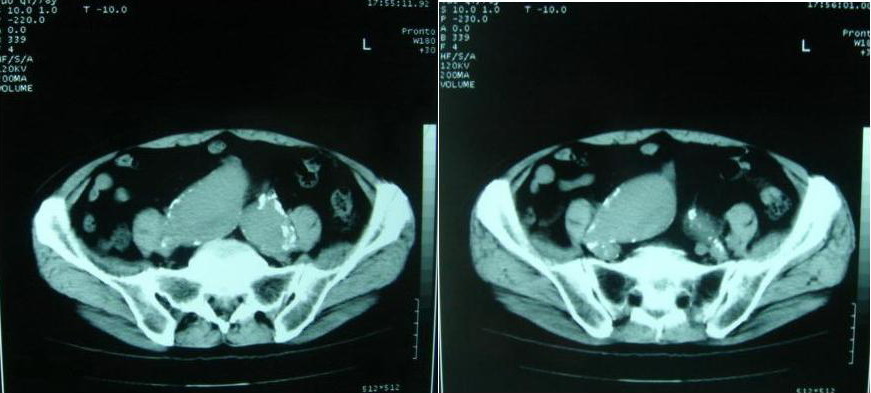

以下是引用借我一双慧眼在2007-8-29 16:24:00的发言:[br]典型腹主动脉瘤累及双侧髂总动脉

以下是引用快乐男生在2007-8-29 16:45:00的发言:[br]腹主动脉及右髂总动脉大范围的管径增粗,[br]管壁多发的钙化,[br]并见真假腔(双腔征),假腔可见附壁血栓.[br]考虑腹主动脉夹层动脉瘤 .建议增强或mri